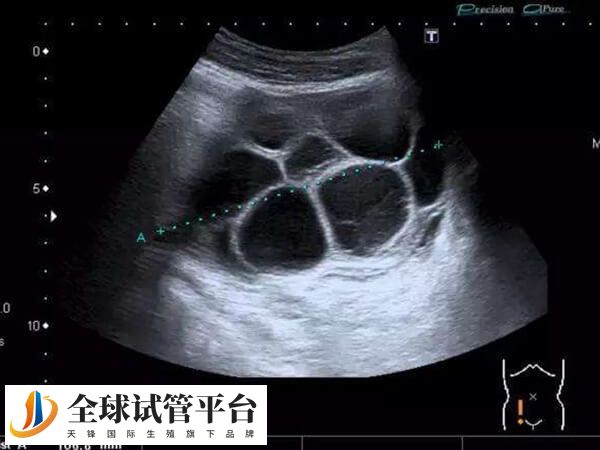

出血是取卵手术最常见的并发症,取卵手术过程中,锋利的穿刺针要经过阴道壁,从卵巢表面刺入,必然会导致一定的出血。不过因个体差异,患者在取卵手术后有淤血块流出,也可能是以下原因。